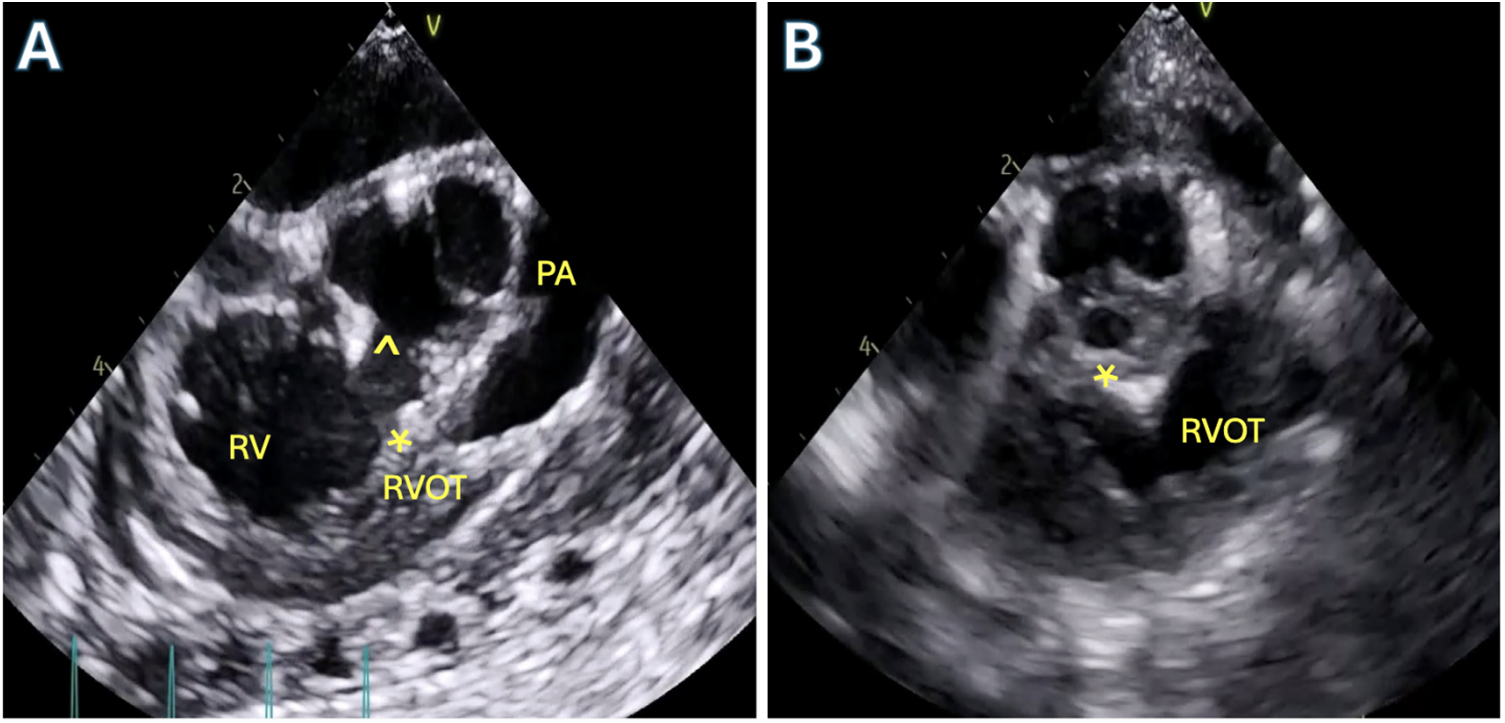

A completion transesophageal echocardiogram is performed to examine residual lesions. Residual VSDs greater than 2–3 mm should be closed as these are unlikely to close in follow up of patients with tetralogy repair [53]. In the presence of optimized pulmonary ventilation and medically optimized pulmonary vascular resistance and equivocal lesions such as residual obstruction, a right ventricular to left ventricular (RV/LV) systolic pressure ratio of greater than 2/3 is generally an indication for further intervention which may include muscle bundle resection, transannular patch creation, extension of right ventriculotomy or patching of discrete branch pulmonary stenosis. In the absence of any addressable lesion, it can usually be safely assumed in the infant that pulmonary vascular reactivity or dynamic obstruction are the etiologies of increased ventricular pressure. The patient is transferred to the intensive care unit for further management. In the absence of fixed obstruction, these patients develop significant improvement in right ventricular pressure and have no long-term mortality effects [54,55]. A pre- and postoperative TEE can be seen in Fig. 7.

Figure 7: Transesophageal echocardiography (TEE) in a patient with Tetralogy of Fallot. A: Pre-operative TEE mid-esophageal right ventricular (RV) outflow tract view showing the anteriorly deviated conal septum (asterisk) with the large ventricular septal defect (VSD,^) and severe sub-pulmonary right ventricular outflow tract obstruction. B: Post-operative TEE after complete repair demonstrating patch closure of VSD (asterisk) and unobstructed right ventricular outflow tract (RVOT)